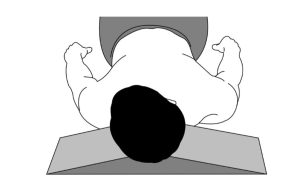

- روشی موثر و راحت در انجام تمرینات دامنه حرکتی فعال (Active ROM Exercise)، استفاده از وسیلهای به نام Occipital Float است که در شکل دو نشان داده شده است.

(شکل شماره ۲ – Occipital Float)

- به تدریج میتوان تمرینات دامنه حرکتی فعال را بر روی یک وسیلهای به نام Foam Wedge و در وضعیت بدون تحمل وزن پیشرفت داد.(شکل شماره ۳) در ادامه میتوان حرکات ترکیبی از خم شدن به جلو و عقب و طرفین و چرخش (فلکشن و اکستنشن و فلکشن طرفی و روتیشن) را نیز به برنامه اضافه کرد.

(شکل شماره ۳)